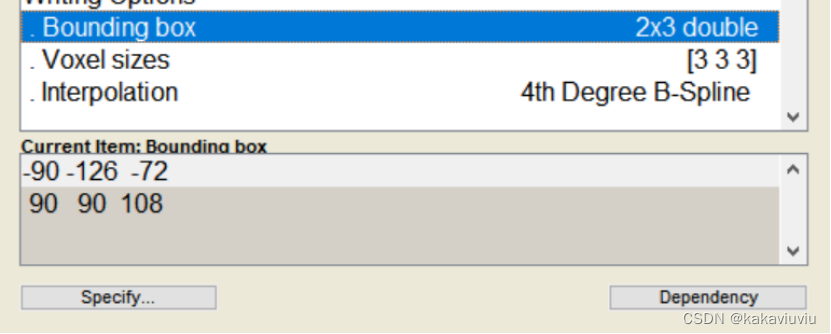

voxel改为3 3 3

设置bounding box边界框:固定值,代表生成文件图像整体的范围是多少

修改boundingbox和体素3 3 3